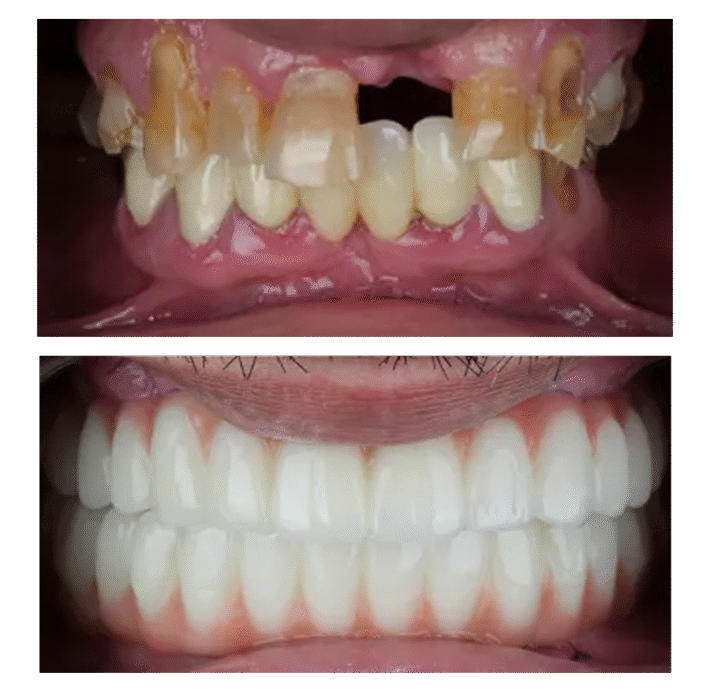

Saving $73,000: How I Got Full Mouth Implants in Vietnam Instead of Paying $100K in the USA All on Four After putting off expensive dental work for two years, I finally went to Vietnam and got 15 teeth pulled and 9 new implants for $27,000 – way less than the $100,000 my local […]

23 Extractions & Full Implants in VietnamHow I Saved 40% and Got My Dream Smile 23 Extractions & Full Implants For anyone considering full mouth reconstruction, I cannot recommend this practice highly enough. They’ve given me the most natural-looking smile of my entire life. Price in Australia $55,000 Price in Vietnam $23,000 Saved $33,000 Saved 60% […]